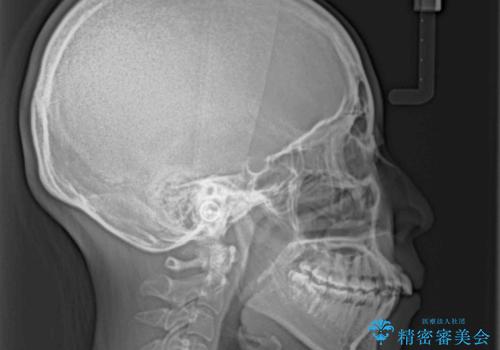

奥歯の噛み合わせをみると、上顎歯列が全体的に前突している状態であり、この咬み合わせのまま歯列を整えると出っ歯になってしまう可能性がありました。

アンカースクリューと補助装置を使用して上顎大臼歯を遠心移動させることで咬み合わせを改善し、更には口元の突出感を改善するために上下左右の小臼歯4本を抜歯し、ワイヤー装置によりデコボコを解消しながら口元の突出感も改善していくこととしました。

上下の前歯が接触する仕上がりとなったので、横顔の印象が大幅に改善されました。